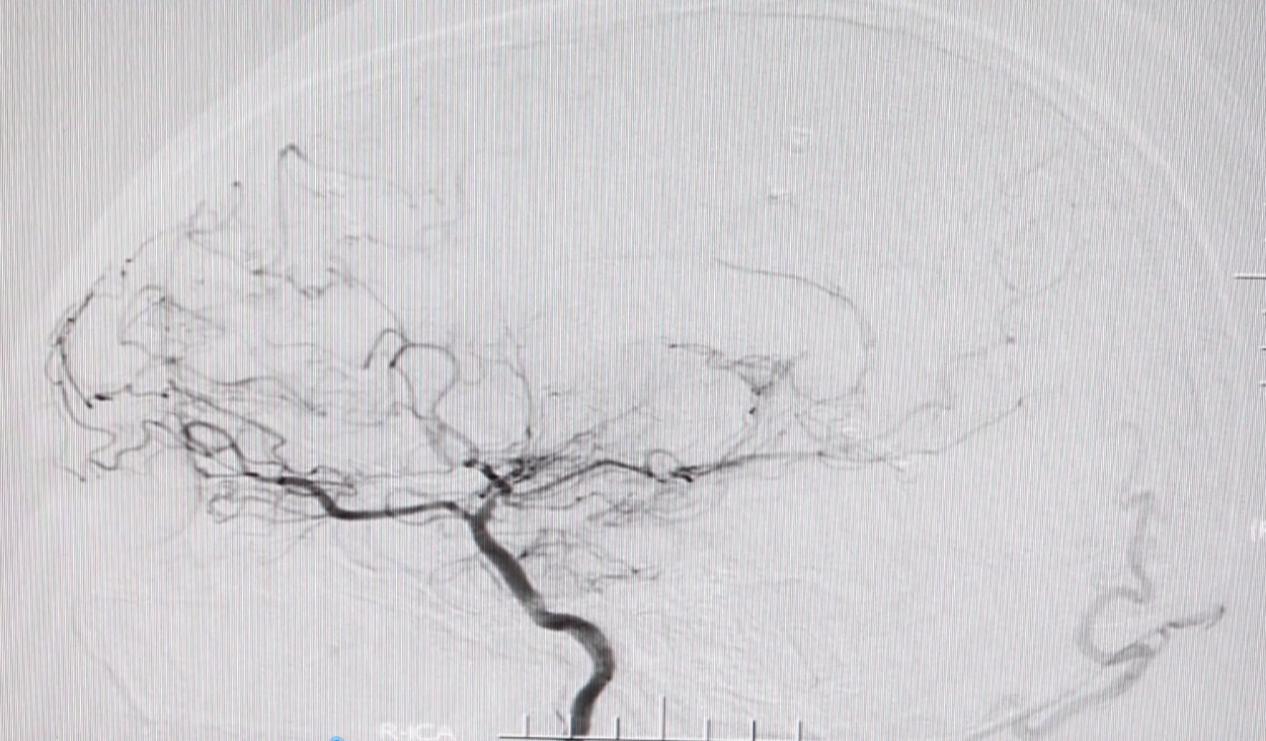

该院接诊的神经外七科主任吾太华仔细查看了陈芳的影像资料,结合病史及数字减影血管造影(DSA)检查结果,认为烟雾病的诊断明确。

“在血管造影下,这类患者大脑血管形态如同重重烟雾,因此形象地称为烟雾病。”吾太华介绍,烟雾病是一种病因不明的脑血管病,容易造成出血或缺血。患者正是因为烟雾病继发脑出血导致双侧枕叶视皮质受损,引起双目失明。